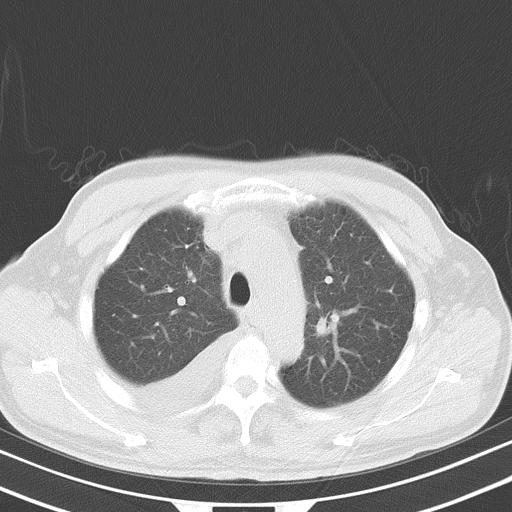

以下是引用zjzjr在2010-3-21 17:39:00的发言:[br]右下中心型肺癌并阻塞性肺炎/不张,纵膈淋巴结肿大,右侧大量胸腔积液,左侧少量胸腔积液

以下是引用zxl51642在2010-3-21 17:06:00的发言:[br]右下中心型肺癌并阻塞性肺炎/不张,纵膈淋巴结肿大,右侧大量胸腔积液,左侧少量胸腔积液,少量腹水。建议纤维支气管镜进一步检查。